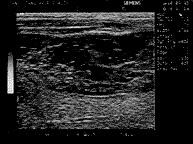

超声检查仪为西门子小狮王,探头频率5~7.5MHz,检查肝表面平整,右肝最大斜径84mm,肝内胆管不扩张。右肝前叶下段及右肝后叶下段分别可见50mm×26mm,61mm×38mm包膜完整之低回声肿块,内部光点分布不均匀,并可见不规则无回声区,其间可见细小光点。两肿块似相通,前者靠近肝表面(图1)。两者分别距第一肝门14mm,距第二肝门23mm,门脉主干内径2.5mm,内清晰。B超诊断:右肝多发巨大海绵状血管瘤可能性大。即日经B超导向穿刺活检,两点取材送检,病理诊断:右肝海绵状血管瘤。

图1 多发性海绵状血管瘤